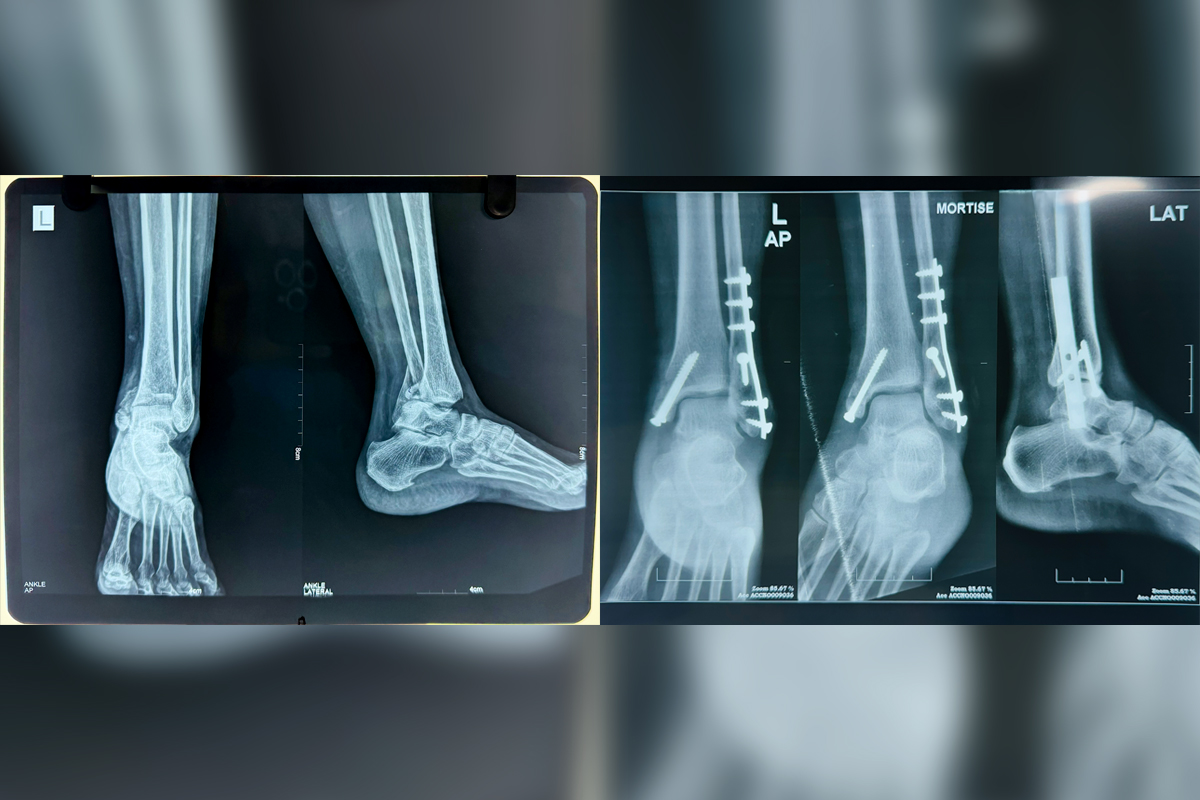

Fractures & Dislocations

Fractures are bone breaks caused by excessive force or trauma, often requiring medical attention and proper care for healing...